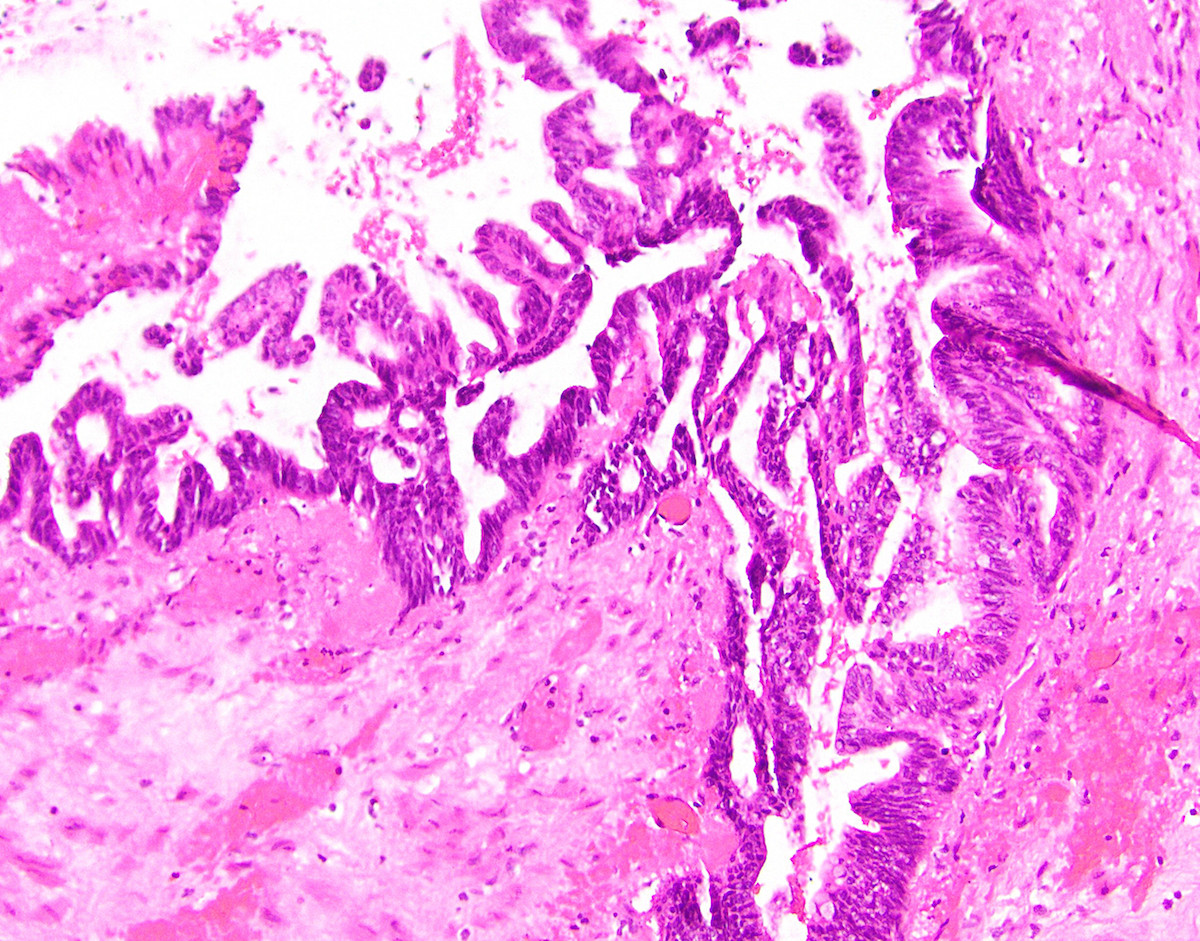

Microscopic (histologic) description

- Villous or occasionally flat proliferation of mucinous epithelial cells originating from appendiceal lumen

- Lesional cells typically demonstrate abundant apical mucin with elongated nuclei and low grade nuclear atypia (LAMN); however, nuclei may appear compressed or rarely high grade (HAMN)

- HAMN may show convoluted architecture, including micropapillary or cribriform features (Histopathology 2020;76:461)

- Often associated with atrophy of underlying lymphoid tissue, crypt loss and effacement of muscularis mucosae

Microscopic (histologic) images

Contributed by Raul S. Gonzalez, M.D. and Michael Feely, D.O.